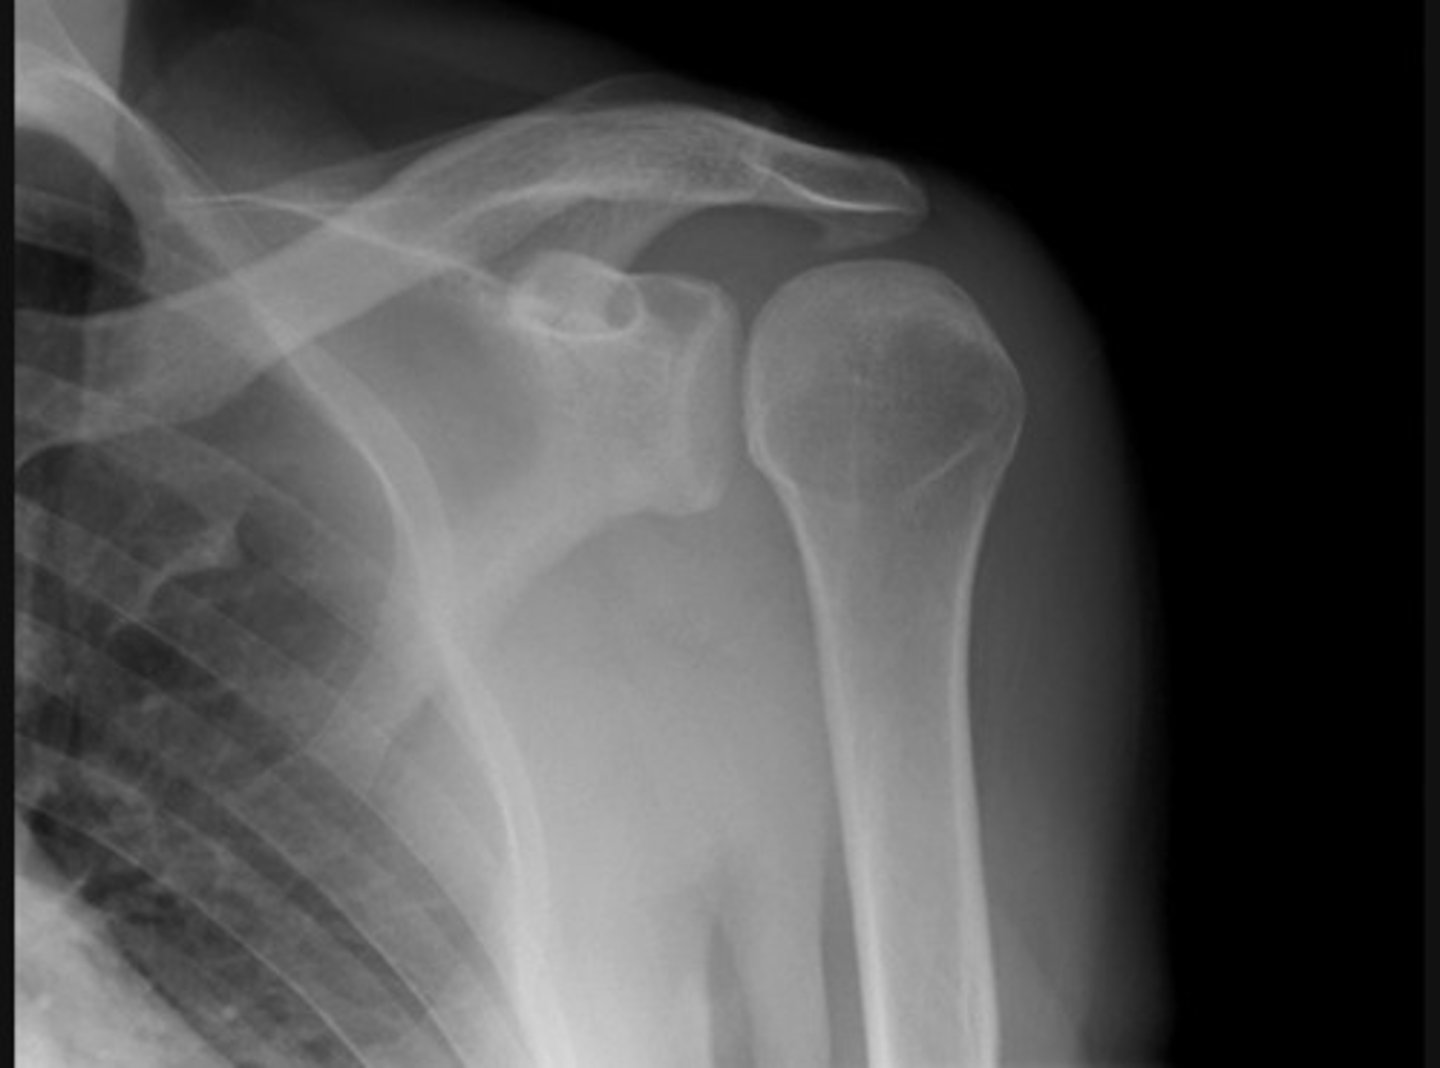

Posterior dislocation, 'lightbulb sign'